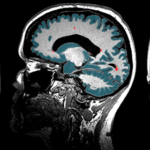

Las causas exactas de la migraña son todavía desconocidas, aunque se cree que son el resultado de una compleja interacción de factores genéticos y ambientales. Se sospecha que una actividad anormal en el cerebro, que afecta los vasos sanguíneos y los nervios, desempeña un papel importante en su desarrollo. Estudios genéticos han identificado varios genes asociados con un mayor riesgo de padecer migrañas, lo que sugiere una predisposición hereditaria. Sin embargo, tener una predisposición genética no significa necesariamente que una persona sufrirá migrañas, ya que también intervienen factores ambientales. La mayoría de los pacientes se ven beneficiados con una correcta selección de medicamento para el dolor de cabeza.